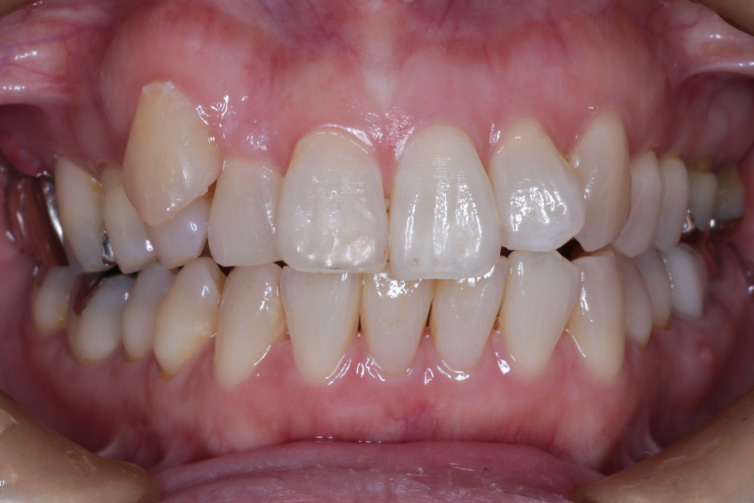

⚫︎年齢:50代

⚫︎性別:女性

⚫︎主訴:八重歯を治療したい。前歯が咬んでないのを治療したい。

⚫︎八重歯が気になる

⚫︎前歯が咬んでいない

⚫︎見た目とセルフケアの不便さ